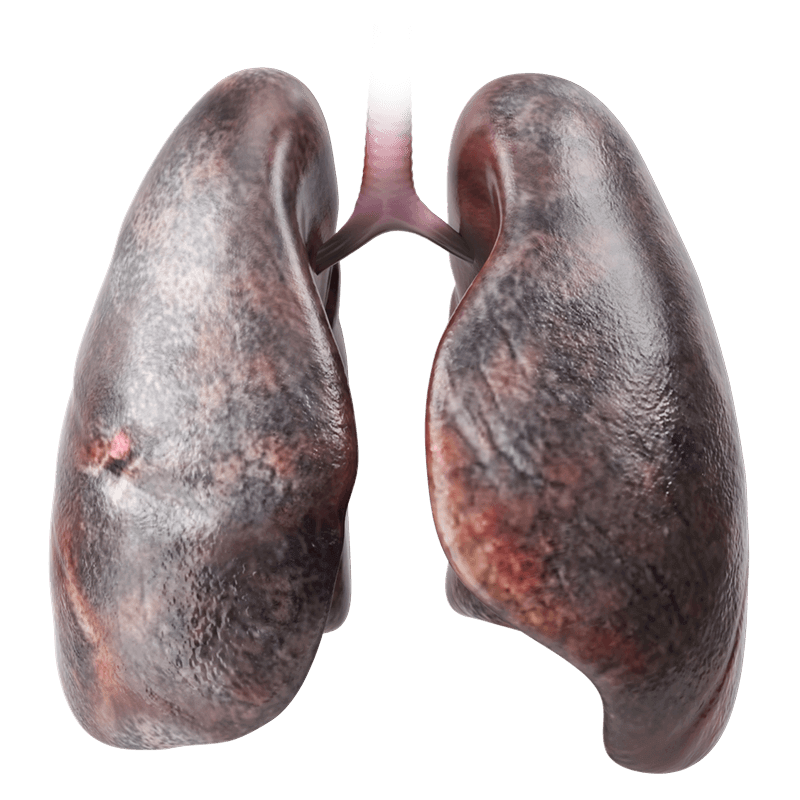

WHICH BODY PARTS CAN VAPING HARM?

The more studies are done, the more dangers are exposed. to see the vital organ damage connected to vaping.